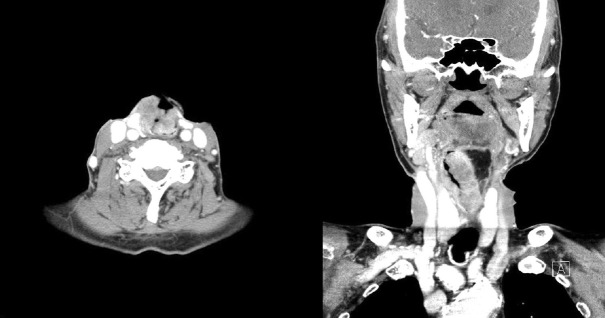

An 82-year-old man diagnosed with supraglottic cancer sought a consultation for percutaneous endoscopic gastrostomy (PEG) placement. Preoperative chest radiography (posterior-anterior [PA] view) revealed no abnormalities, and PEG tube placement was performed using the "pull" method. Chest radiography (PA view) performed 3 days postoperatively showed free air that was not observed immediately after PEG tube placement; therefore, the patient was diagnosed with pneumoperitoneum. Abdominal computed tomography confirmed that the PEG tube was appropriately positioned within the stomach; however, the colon was observed between the abdominal wall and stomach, which indicated that the PEG tube had passed through the colon. Review of preoperative chest radiographs (PA views) confirmed that the colon was visualized in the area wherein usually stomach gas should have been observed. The patient was diagnosed with a gastro-colo-cutaneous fistula that occurred postoperatively, following a procedure that was performed without confirmation of anatomical variations. The PEG tube was removed surgically, and we performed percutaneous gastrostomy.

一个82岁的男性诊断为声门上癌寻求咨询经皮内镜胃造口术(PEG)安置。术前胸片(后-前[PA]面)未见异常,采用“拉”法置入PEG管。术后3天胸片(PA视图)显示PEG管置入后未立即观察到自由空气;因此,患者被诊断为气腹。腹部计算机断层扫描证实胃内PEG管位置正确;然而,在腹壁和胃之间观察到结肠,表明PEG管已通过结肠。术前胸部x线片(PA视图)证实结肠出现在通常应该观察到胃气的区域。该患者被诊断为胃-结肠-皮肤瘘,发生在术后,在没有确认解剖变异的情况下进行了手术。手术取出PEG管,我们进行了经皮胃造口术。